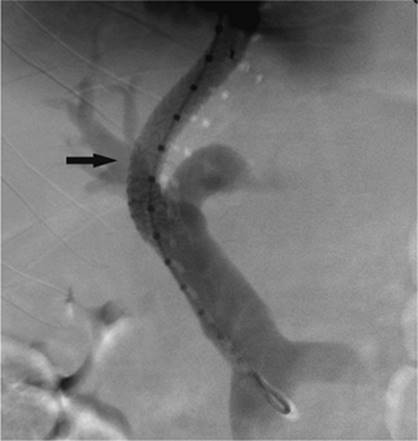

Figure 35.16. Patient presents with biliary obstruction. On hospital day 1, external drainage has been achieved using a right-sided bile duct approach. Cholangiogram shows complete obstruction in the mid common bile duct (CBD) (black arrow).

The indications for percutaneous biliary drainage include palliation of an unresectable primary or secondary malignancy of the liver causing biliary obstruction, benign strictures including biliary-enteric anastomosis as seen in liver transplant patients, sepsis secondary to biliary obstruction, preoperative decompression, stone removal, bile leak after laparoscopic cholecystectomy, biopsies, permanent internalization of drainage by placement of internal stent, and radiation therapy (29) (Figs. 35.18 and 35.19).

Figure 35.17. On hospital day 2, internal/external drainage has been achieved by gaining access to the small intestine across the area of obstruction.

000250

Figure 35.18. This is the same patient as in Figures 35.16 and 35.17. A metallic self-expanding stent has been placed across the area of obstruction in the distal common bile duct. Note the waist in the stent (black arrow) due to the surrounding mass.

000446

Figure 35.19. Post–stent placement and balloon angioplasty. No residual stenosis is noted, and the stent is fully expanded.